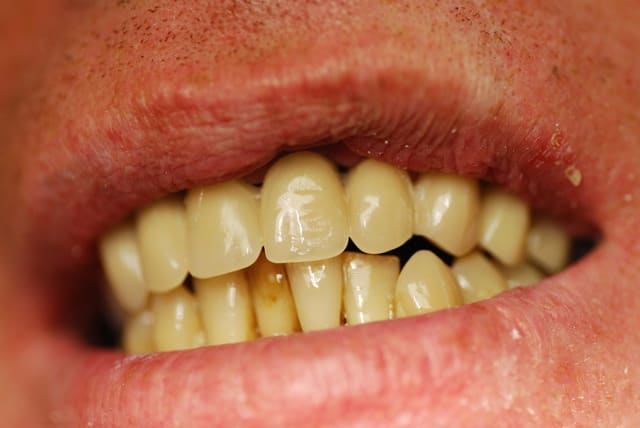

Je viens de revoir le patient et je peux vous apporter quelques précisions ainsi que des photos( désolé si la qualité n'est pas parfaite).

Patient de 45 ans, fumeur, motivé mais ne pouvant se payer d'implants.

Il a déjà vu plusieurs confrères qui lui ont proposé uniquement ( selon ses dires) une solution implantaire pour 12-11-21-22-23. Il souhaite du fixe...

Une photo du sourire peut t'aider à savoir si l'esthétique " rose" est primordiale ou non chez ton patient; si il a un sourire gingivale, vous allez en chier pour l'améliorer.